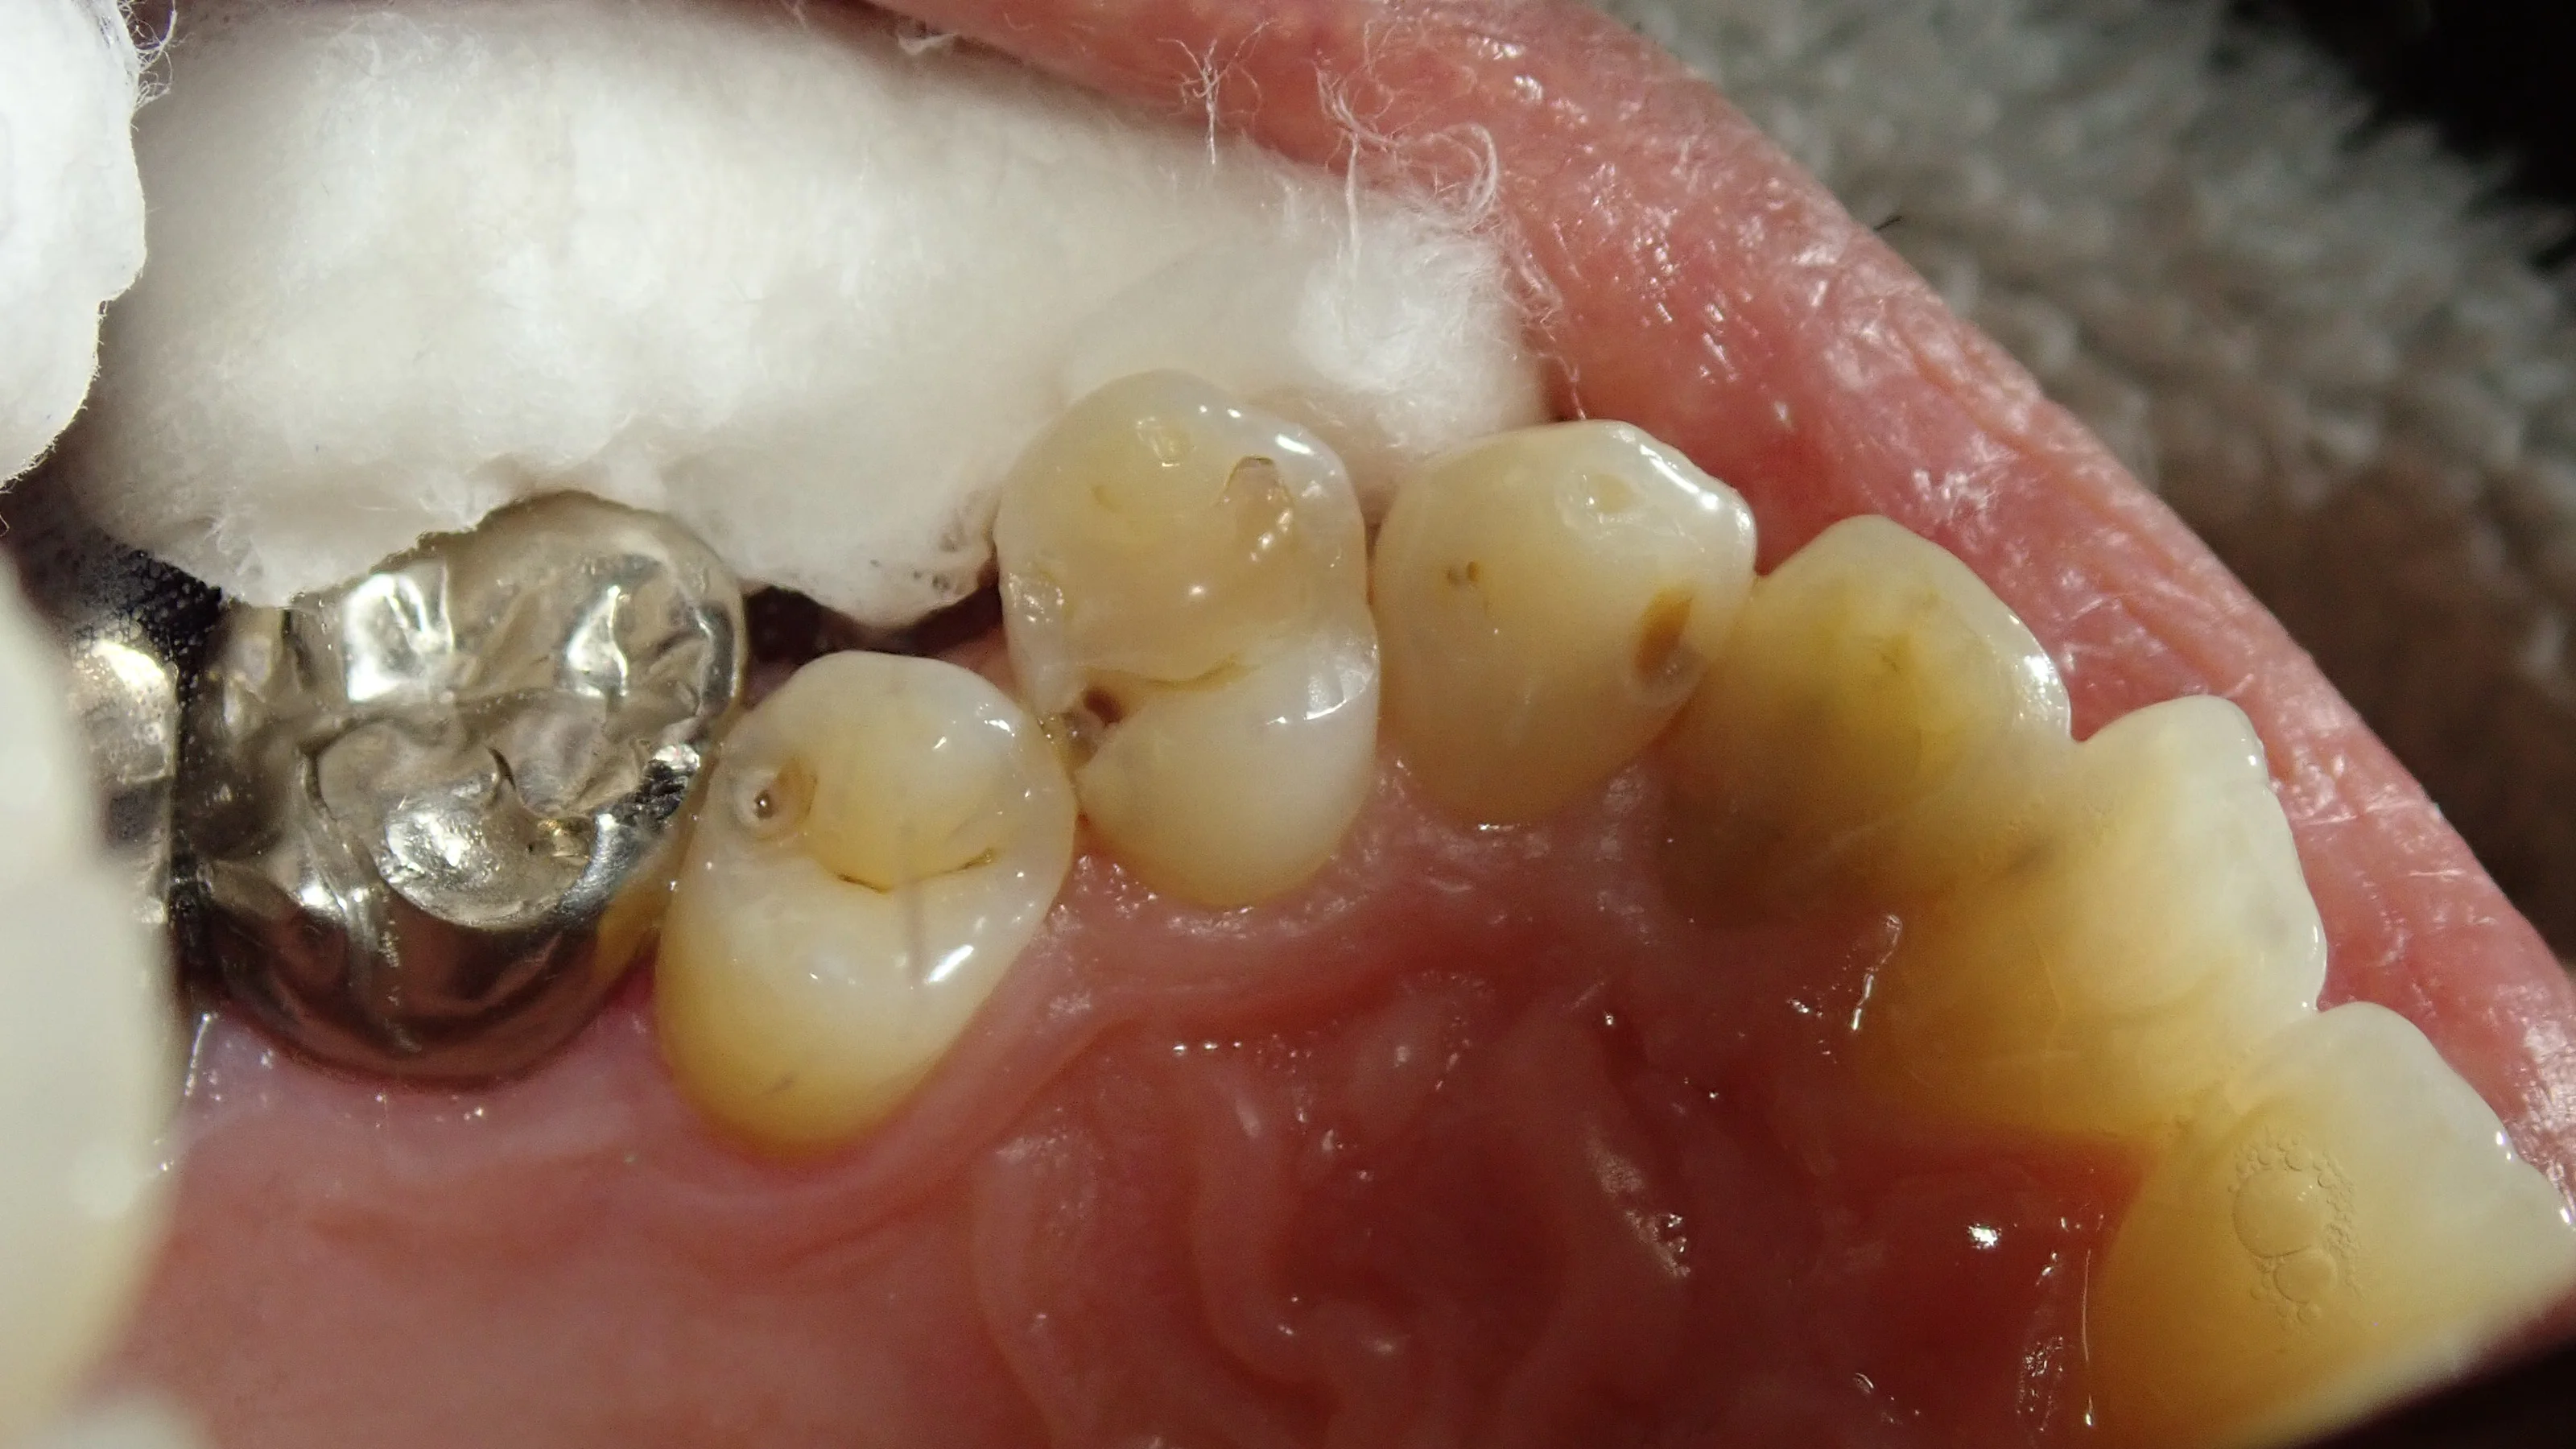

さて、今回は、ダイレクトボンディングの症例紹介を行っていきます。

行うのは画面中央にある歯3本です。

真ん中の詰め物の部分は虫歯が非常に分かりやすいかと思いますが、それ以外の場所は少し分かりづらいかもしれませんね。